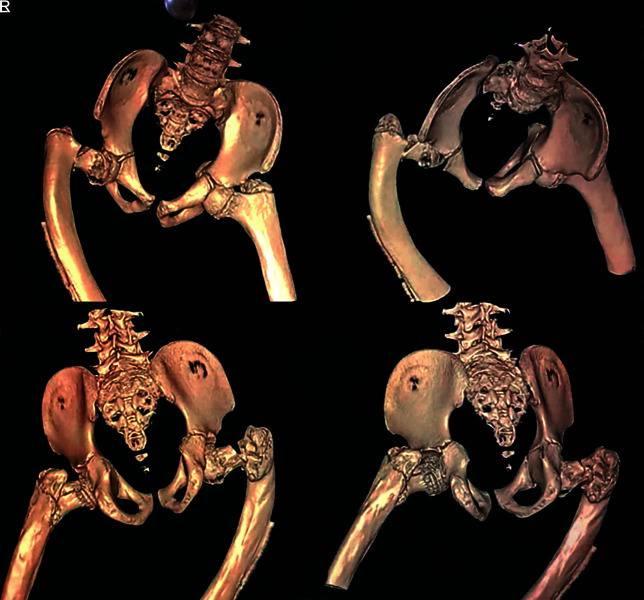

Osteogenesis imperfecta (OI) patients usually sustain repeated fractures from trivial trauma and also have skeletal deformities that affect walking. The bone fragility and repeated fractures produce deformities of the long bones especially in femur and tibia. However, neck of femur (NOF) fractures in OI are rarely described. A 11-year-old male patient known to have OI (Sillence type IV) sustained a NOF fracture after a fall. He also had proximal femoral anterolateral bowing proximally and over an intramedullary (IM) rod inserted 4 years back. He was treated by corrective osteotomy and stabilisation with an IM telescoping nail for the deformed femur and the Wagner technique for the NOF fracture. One year after operation, the patient had recovered satisfactory functional outcome with union of the NOF fracture and correction of the femoral deformity.

Conclusion: The method of the Wagner technique can achieve stable fixation for femoral neck fractures and introduces the least interference with concurrent telescoping nail insertion.